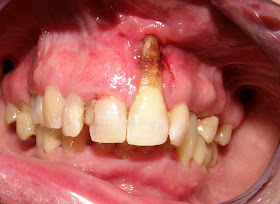

Receding gums also known as gum/ginigival recession, refers to exposure in the roots of the teeth caused by a loss of gum tissue. In a healthy mouth the gums along with the periodontal connective tissue surround and support the tooth in the jawbone. Gum recession usually involves a significant loss of these protective tissues. The gum line is pulled away from the root allowing a larger part of the tooth to be visible and in contact with the mouth’s environment. Gum recession is not something that happens overnight. In most cases, receding of gums is a progressive procedure that happens gradually from day to day over the years.

Severe gum recession and calculus buildup - LINK